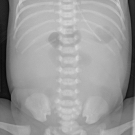

Geethika Thota, MD; Niraj Ballam Nagaraj, MD

A 39-year-old woman with no significant medical history presented to the emergency department reporting low back pain, nausea, and vomiting for 1 day.